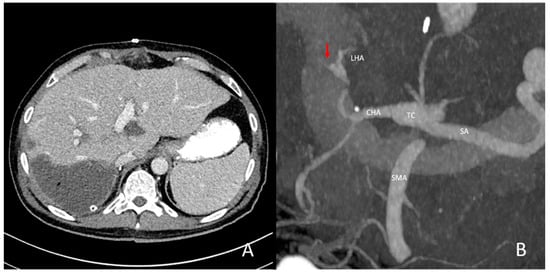

3.2. Vascular Findings—Anatomic Variants and Pre-Existing Pathologies of the Hepatic Vasculature

3.3. Analysis of Types and Occurrences of Arterial Complications